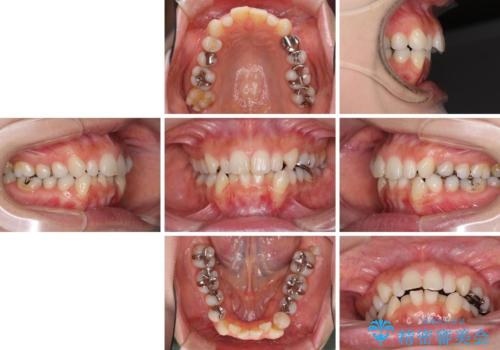

- 前歯のデコボコと矮小歯、更には痛みを感じる奥歯のむし歯を気にして来院された患者様です。

奥歯には根管治療が必要な歯があり、上顎側切歯は左右ともに矮小歯でした。

上下前歯のデコボコはワイヤーでもインビザラインでも対応可能でしたが、補綴治療が多く必要となることから、インビザラインでの矯正治療を行いながら、並行して補綴治療を行うこととしました。

まずは根管治療を行った上で矯正治療用の仮歯を装着し、矯正治療後半に補綴治療を並行して行うこととしました。

複数歯の補綴治療を行う場合、仮歯やセラミッククラウンを装着する度に保定装置を作り替える必要があり、その度に後戻りを起こす可能性が高くなります。

インビザラインであれば、矯正治療後半で補綴治療を行い、その後矯正治療を継続することでスムーズに治療を終えることができます。